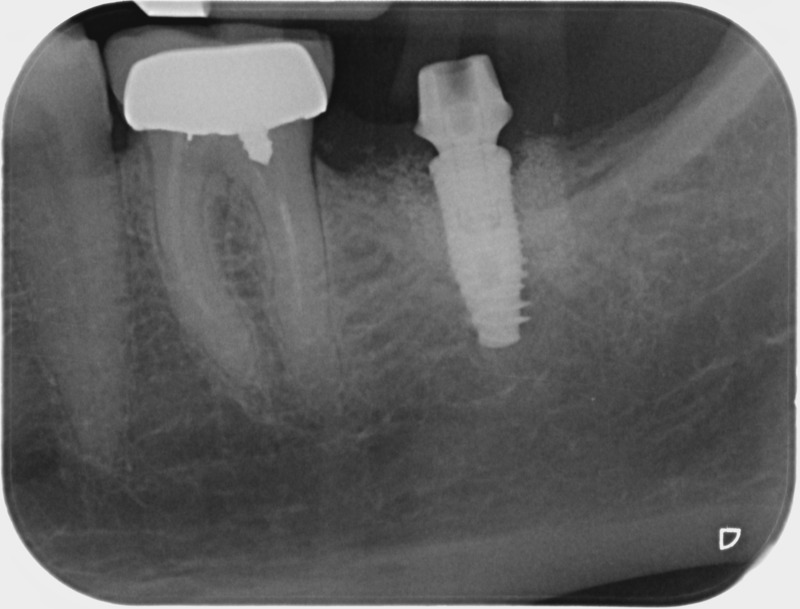

• Couronnes sur implants : Lorsqu’un implant est posé en remplacement des racines d’une dent, il est conçu pour recevoir d’abord un pilier vissé puis une couronne céramique. Le couple couronne - implant se substitue à la dent manquante pour en assurer les mêmes fonctions. Nous pouvons également adapter un bridge sur plusieurs implants dans le cas d’un édentement plus important.

Avant